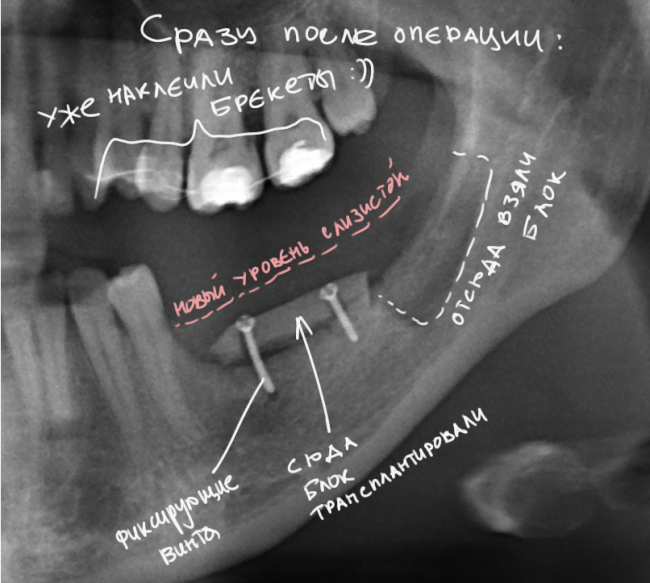

Вот снимок после операции:

И с обозначениями:

«Пустое пространство» под блоком мы заполнили аутокостной стружкой, а сверху закрыли барьерной мембраной BioGide. Самое сложное в данной работе было, на мой взгляд, подогнать размер блока, «собрать» слизистую оболочку и наложить швы так, чтобы пациентка не кусала послеоперационную рану верхними зубами. Кстати, как видите, на верхние зубы уже наклеили брекеты — начали ортодонтическое лечение.